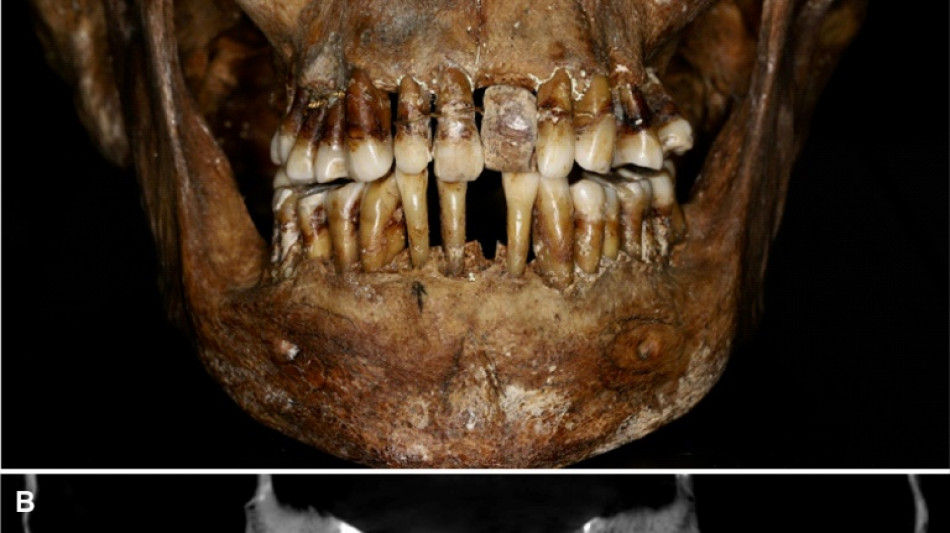

La dentition d'une aristocrate du XVIIe siècle comme marqueur social / Photo: © INRAP/AFP

La sépulture d'Anne d'Alègre, morte en 1619 à l'âge de 54 ans, avait été déterrée lors d'une fouille au château de Laval, en 1988. Embaumé dans un cercueil de plomb, le squelette était particulièrement bien conservé, sa dentition aussi.

Plus de trente ans après, une équipe comprenant des archéologues et des dentistes dévoile qu'Anne d'Alègre était atteinte d'une maladie parodontale qui provoque le déchaussement progressif des dents, selon une étude parue cette semaine dans Journal of Archeological Science.

Les images radiologiques par "Cone Beam", un scanner en 3D, montrent que la patiente portait une prothèse dentaire remplaçant une incisive, soutenue par des fils d'or, ainsi qu'une ligature de contention sur des pré-molaires.

Des examens en macroscopie ont déterminé que cette prothèse était en ivoire d'éléphant, écartant la piste de l'ivoire de dents d'hippopotame, également utilisé à l'époque.

Ce traitement n'a fait "qu'aggraver la situation" de la patiente, explique à l'AFP Rozenn Colleter de l'Inrap (Institut national des recherches archéologiques préventives), auteure principale de l'étude.

A long terme, ce traitement, ainsi que les "multiples resserrages nécessaires, ont entraîné l'instabilité des dents voisines", détaille l'Inrap.